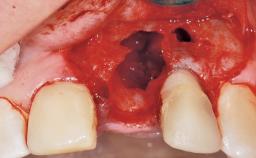

Immediate Flapless Placement of an Implant in a Maxillary Left Central Incisor Site

A 42-year-old female patient was referred to our clinic at the School of Dentistry of the University of São Paulo in November 2004, presenting a deficient restoration in the upper left central incisor. The clinical examination revealed no gingival retraction or any signs of gingival inflammation and, therefore, previous periodontal treatment was not considered. The patient presented a high lip line at full smile and a thin tissue biotype. This combination characterized a high-risk situation from an anatomic point of view, which required careful preoperative planning and cautious surgical execution.

Placement Protocol Immediate implant placement

Socket Morphology Single-root socket

Socket Integrity Sufficient, with intact bone walls

Bone Volume Sufficient, with intact walls